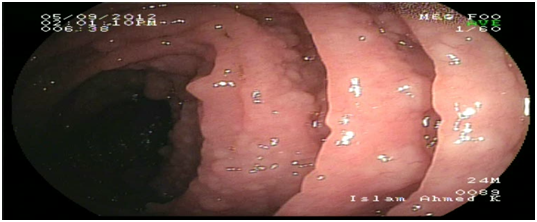

Abdominal ultrasound showed uniform circumferential mural thickening of the small bowel loops, so we proceeded to C.T Enterography. As shown in Figure 1, there is diffuse uniform thickening of the small bowel loops mainly involving the ileum with no focal thickening or masses. Then upper endoscopy and colonoscopy were performed to the patient and they showed multiple tiny rounded nodules at the terminal ileum that were biopsied and revealed non-specific inflammation free of granuloma or malignancy. Then we proceeded to double balloon enteroscopy which was done by an over tube double balloon Fuji series endoscopy, which proceeded to about 200cm from the duodenal bulb. Double balloon endoscopy as shown in Figure 2, showed numerous visible mucosal nodules measuring few millimeters in diameter involving the whole part of the small intestine examined which were biopsied. Histopathology revealed chronic inflammatory enteritis with foci of lymphoid aggregates with no atypia or malignancy (Table 1).

Figure 2 Diffuse small nodules scattered through the whole small intestine by double ballonenteroscopy.

Some reports had described DNLH in adult patients without immunodeficiency and it was thought to be associated with chronic GIT infections such as Giardiasis or Helicobacter pylori infection.4,8,10 Nodular lymphoid hyperplasia generally presents as an asymptomatic disease, but it may cause gastrointestinal symptoms like abdominal pain, chronic diarrhea, malabsorbtion syndrome, bleeding or very rarely intestinal obstruction.5 One of the most important issues likely to be raised is the differential diagnosis of this condition. Due to its characteristic appearance during endoscopy which appears as innumerable small nodules involving mainly the small intestine as shown in Figure 2 limits the differential diagnosis. Familial adenomatous polyposis (FAP) and intestinal lymphoma should be taken into consideration. GIT is considered the largest lymphoid system in the body, so intestinal diseases are not surprisingly associated with the immunodeficiency syndromes. Common variable immune deficiency is defined as deficiency of immunoglobulins mainly IgG associated with IgA, IgM or both.6 Selective IgA deficiency syndrome (SIgAD) is the most common primary immunoglobulin deficiency and is defined as the isolated deficiency of serum IgA (ie, in the setting of normal serum levels of IgG and IgM) in a patient whom other causes of hypogammaglobulinemia have been excluded.6–9 About 10 -15 % of the patients with SIgAD have symptoms of recurrent sinopulmonary infections, autoimmune disorders, gastrointestinal infections, anaphylactic transfusion reactions, Food allergies and respiratory allergies are prominent.6–9 There is an increased risk of malignancy in patients with DNLH and a coexisting hypogammaglobulinemia, especially the risk of lymphoma and gastric carcinoma. This is the typical scenario of our patient that was diagnosed after his presentation with intestinal lymphoma.11 DNLH with no complications usually does not require any special treatment. However, the patients should undergo the prophylactic examinations. For patients with chronic diarrhea repeated courses of antibiotics such as quinolones or metronidazole had been reported. Also eradication of Helicobacter pylori had significant reduction in the number and size of the nodules in some studies.4–12 This causes controversy when deciding the treatment options. Following up patients without any treatment may lead to malignant progression, while surgical treatment may result in justified radical resections.